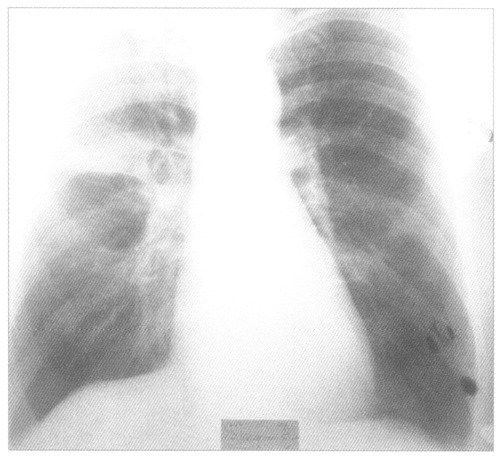

Рентгенологическое исследование органов грудной полости выявляет затемнение пораженного участка легкого. Плотность тени, ее расположение, очертания и размеры меняются в зависимости от локализации очага воспаления и степени его распространения. Исчезновение последних следов поражения легкого наступает через 1—2 недели после кризиса. Рентгенологическое исследование имеет особое значение при центральной пневмонии, а также для раннего обнаружения осложнений.

Крупозная пневмония на рентгенснимке